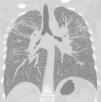

Case 2A 50-year-old man, non-smoker, who since 1981 has worked in the same company as Case 1, performing similar tasks. Since 2000, he has intensively used artificial quartz conglomerates for constructing kitchen and bathroom surfaces. The patient was asymptomatic and lung function test results were normal. Chest X-ray was performed twice, in 2011 (during routine medical examinations ordered by the company) and in 2013 (Fig. 1). In 2011, ILO classification showed nodular q-p opacities with 2/2 profusion in both lungs, mainly in the upper and middle lung zones. In 2011, lung HRCT according to ICOERD classification showed prevalent well-defined rounded grade 2 opacities, predominantly size q, profusion grade10 (Fig. 2). The patient was assigned to different tasks in order to prevent further exposure, but in 2013 the radiographic abnormalities according to ILO classification had increased (q/r opacities with profusion 2/3 in both lungs and large type A opacities). ANA and anti-ENA levels were normal. QuantiFERON testing for Mycobacterium tuberculosis was negative. Mycobacteria detection with direct microscopy, culture and PCR, and bacterial and mycological culture of BALF were all negative. Cell count showed lymphocytosis (41%) and a decreased CD4+/CD8+ratio.